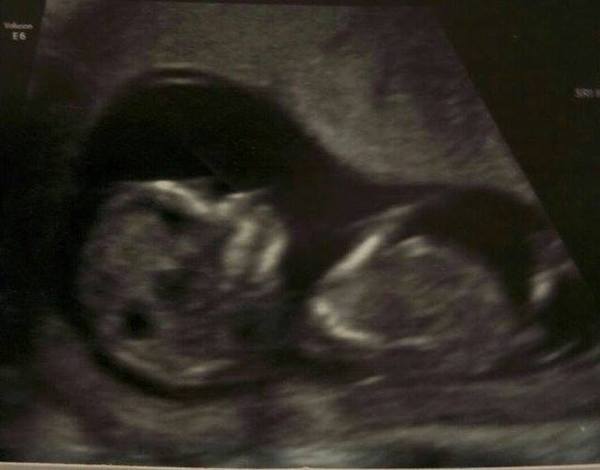

However, I went for my 12-week scan last Friday and despite the baby's impromptu in-uterus breakdancing routine making it hard to get a clear image, it was all PERFECT. Measuring bang on the original dates (minus one day) and all looked delightful. EDD is now Nov 5th, but the teenage goth in me is hoping he or she will make an appearance on halloween :D